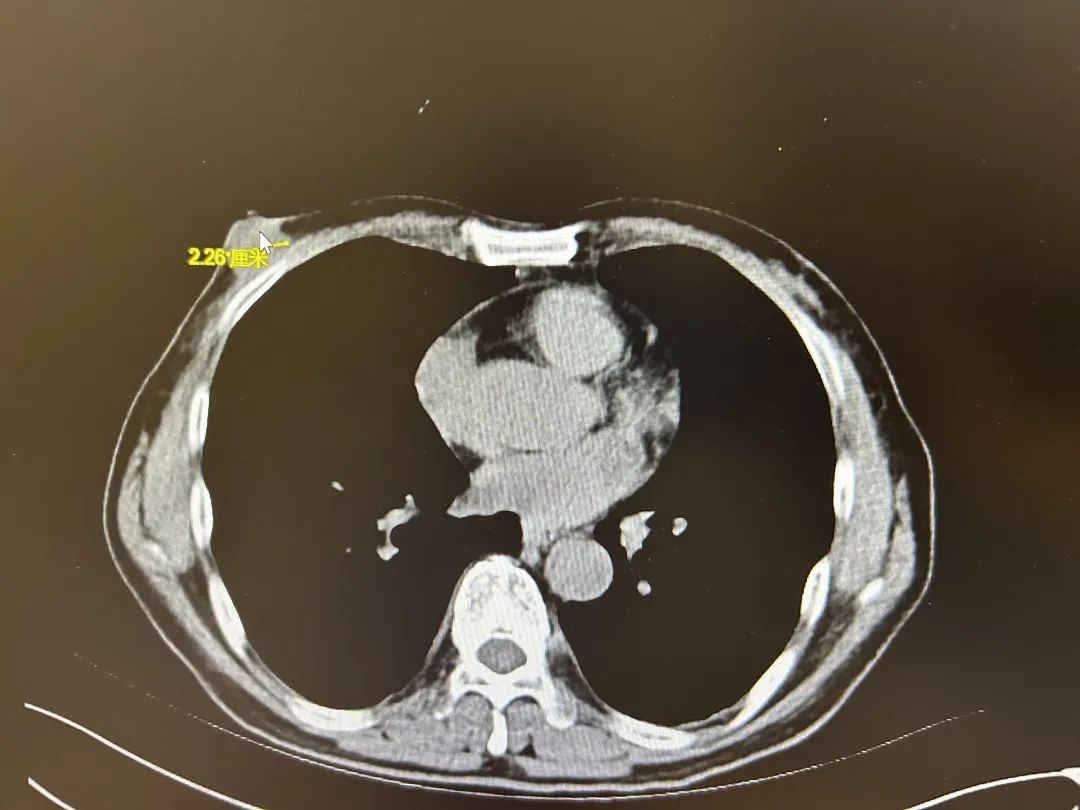

影像报告显示,张老伯的右乳有一个直径约为2厘米的肿块,初步诊断考虑是乳腺恶性肿瘤,不及时切除有转移风险。经术后病理检查,确诊张老伯为乳腺癌。一段时间的治疗后,目前张老伯恢复良好,进入术后辅助化疗阶段。

影像报告显示2厘米的乳腺肿瘤